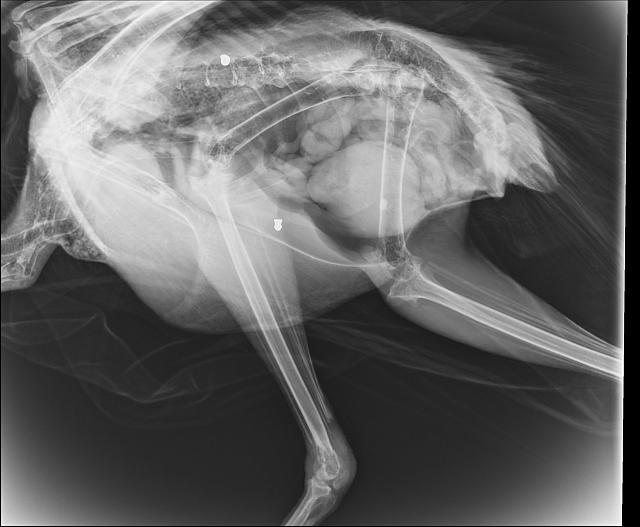

Με έκπληξή μας, εμφανίζοντας την ακτινογραφία, είδαμε δυο βολίδες αεροβόλου κι ένα σκάγι μέσα στο σώμα του!

Το πτηνό  έχει πυροβοληθεί τρείς φορές, την ίδια ώρα ή διαφορετικές δεν μπορούμε να ξέρουμε, ούτε αν ο δράστης είναι ένας ή δύο ή τρεις, μέσα ή δίπλα σε έναν από τους πιο πολυσύχναστους αρχαιολογικούς χώρους της Κρήτης και της Ελλάδας γενικότερα.